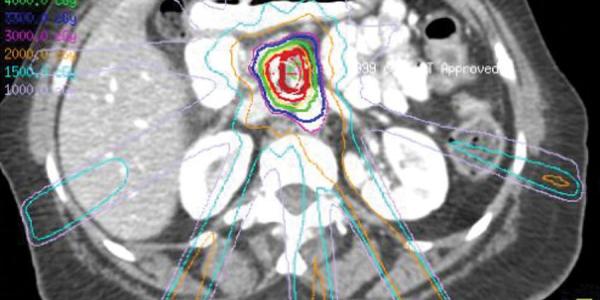

Los tratamientos con radioterapia curan entre el 40 y el 90 % de los tumores de cabeza y cuello

Los principales factores de riesgo para el desarrollo de un tumor de cabeza y cuello son el tabaco, el alcohol y el virus del papiloma humano.